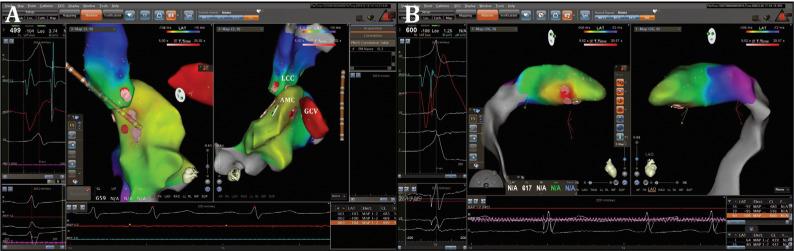

The left ventricular (LV) summit is the usual source of epicardial idiopathic premature ventricular contractions (PVCs). A 56-year-old male patient presented to the cardiology outpatient clinic with palpitations and dyspnea. Twelve-lead electrocardiography performed on admission revealed monomorphic PVCs with precordial QRS transition in the V1 derivation and an rS pattern in the D1 derivation and inferior axis. An electrophysiology study and ablation procedure were planned. Activation mapping guided by a three-dimensional electroanatomic system was conducted to identify the earliest site of ventricular activation of the PVCs. During the PVCs, the earliest ventricular activation was observed within the great cardiac vein (GCV) and preceded the QRS onset by 37 ms. Coronary angiography was performed before ablation in the coronary venous system (CVS) to assess the distance from the coronary artery, which showed severe stenosis in the left circumflex artery. Then, percutaneous coronary intervention was performed to address the left circumflex artery stenosis. Anatomic catheter ablation was performed in the aortic cusp and endocardial LV outflow tract, the sites adjacent to the LV-summit PVC origin. However, successful ablation could not be achieved. Subsequently, an irrigated radiofrequency current was delivered in the GCV for 60 seconds, with the power being gradually increased to 30 W and with an irrigation flow rate of 30 mL/min. After ablation, under isoproterenol infusion and burst pacing from the right ventricle, no PVC or ventricular tachycardia was observed. Special precautions should be taken to avoid coronary artery damage during ablation from distal CVS. This approach may increase the success of ablation and avoid potential complications.

左心室(LV)峰是心外膜特发性室性早搏(PVCs)的常见起源部位。一名56岁男性患者因心悸和呼吸困难就诊于心脏病门诊。入院时进行的12导联心电图显示单形性PVCs,胸前导联QRS波在V1导联移行,D1导联呈rS型且电轴下偏。计划进行电生理研究和消融手术。采用三维电解剖系统引导下的激动标测来确定PVCs最早的心室激动部位。在PVCs发作期间,最早的心室激动出现在大心脏静脉(GCV)内,比QRS波起始提前37毫秒。在冠状动脉静脉系统(CVS)进行消融术前进行冠状动脉造影,以评估与冠状动脉的距离,结果显示左旋支动脉严重狭窄。随后,进行经皮冠状动脉介入治疗以处理左旋支动脉狭窄。在主动脉瓣尖和左心室流出道内膜进行解剖性导管消融,这些部位与LV峰PVC起源相邻。然而,未能成功消融。随后,在GCV内输送灌注射频电流60秒,功率逐渐增加至30W,灌注流速为30mL/min。消融后,在静脉滴注异丙肾上腺素和右心室猝发起搏时,未观察到PVC或室性心动过速。在从远端CVS进行消融时,应特别注意避免冠状动脉损伤。这种方法可能会提高消融成功率并避免潜在并发症。